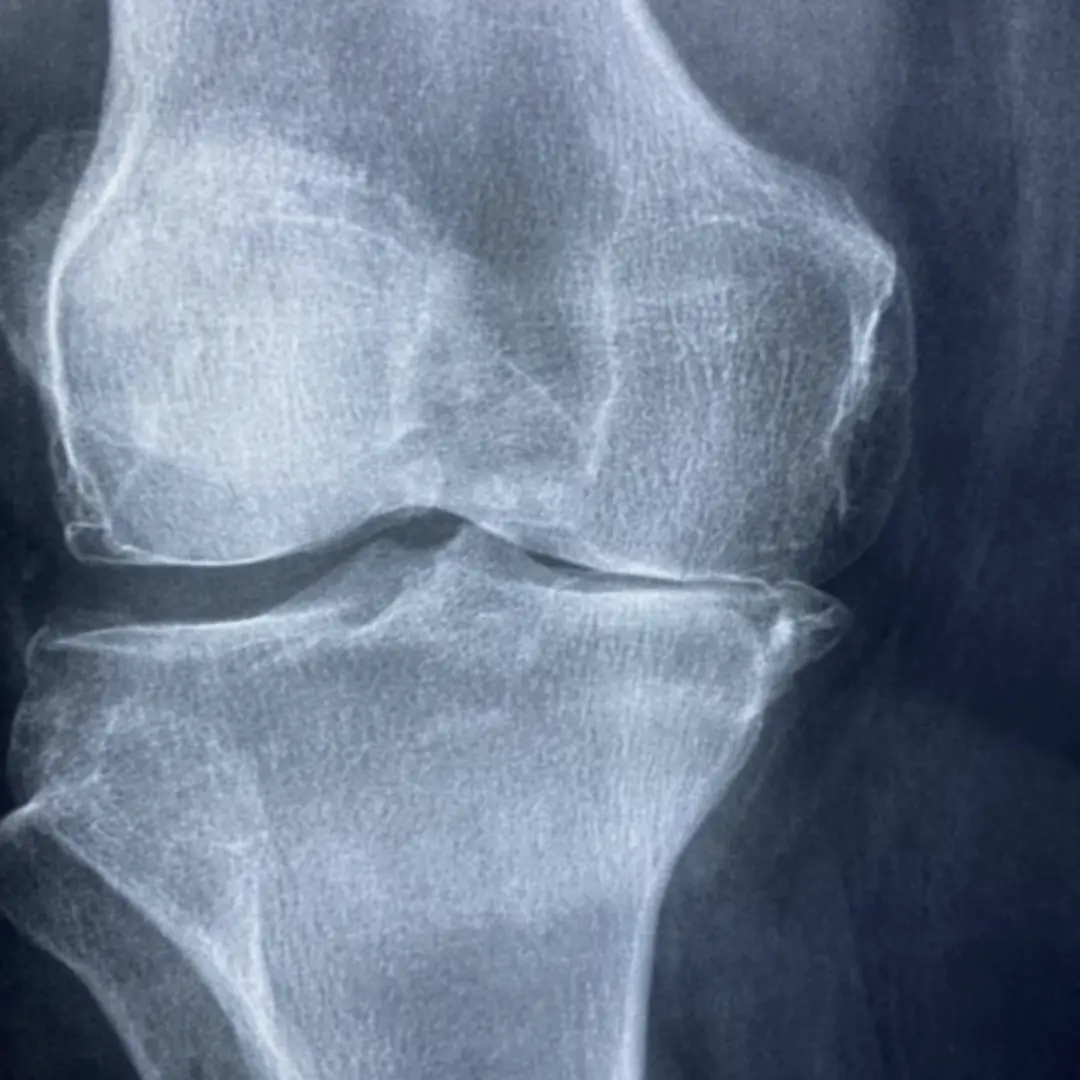

- 관절염 (골관절염): 가장 흔한 무릎 통증의 원인이에요. 나이가 들면서 무릎 관절의 연골이 닳아 없어지면서 뼈와 뼈가 직접 부딪히고 염증이 생겨 통증을 유발해요. 아침에 뻣뻣하고, 움직일 때 통증이 심해지며, 뼈 마찰음이 들리기도 합니다.

- 퇴행성 관절염 (골관절염):

- 원인: 관절 연골이 점진적으로 손상되거나 퇴행성 변화를 겪으며 발생해요. 나이, 비만, 과사용, 과거 외상 등이 주요 원인입니다.

- 증상:

- 움직일 때 뻑뻑한 느낌이나 마찰음이 나요.

- 아침에 일어나거나 한 자세로 오래 있다가 움직일 때 **뻣뻣함(조조강직)**이 나타나요.

- 활동량이 많을수록 통증이 심해지고, 쉬면 완화되는 경향이 있어요.

- 무릎이 붓고 열감이 느껴질 수 있습니다.